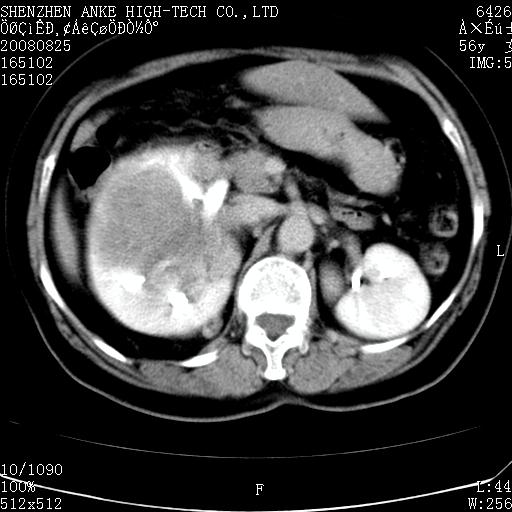

患者,女性,56岁,腰痛3年,查:右腹部约8x10cm肿块,固定,无压痛;8月23日在外院做了平扫,发现右肾巨大肿块(外院具体诊断不祥);今天在我院做了静脉肾盂造影,示:右肾明显增大,分泌功能明显减弱。

右肾癌可能大。

支持右巨大肾癌。

1)考虑右肾癌并右肾静脉瘤栓形成。2)脂肪肝。